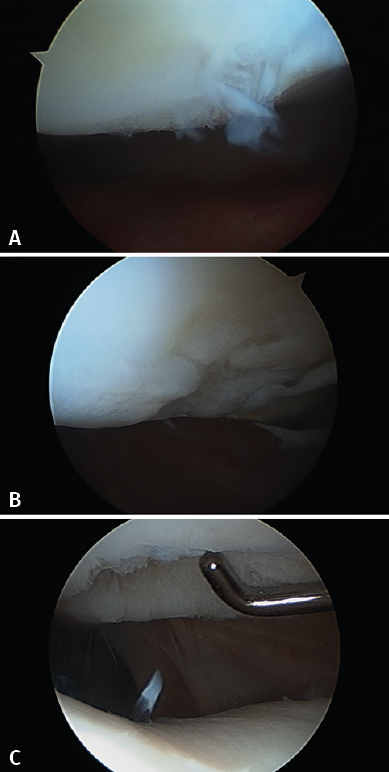

Although there are a number of classifications for assessing the degree of joint cartilage damage, the most widely used option is the classification of Outerbridge (1961), which defines four grades(5,6) (Figure 3):

• Grade I: softening or edema of the cartilage surface.

• Grade II: fissures or fragmentation affecting a surface of less than 1.25 cm in diameter.

• Grade III: fissures or fragmentation affecting a surface of over 1.25 cm in diameter.

• Grade IV: erosion of the cartilage extending to the subchondral bone.

Figure 4 shows arthroscopic images of lesions corresponding to grade II (Figure 4A), grade III (Figure 4B) and grade IV (Figure 4C).